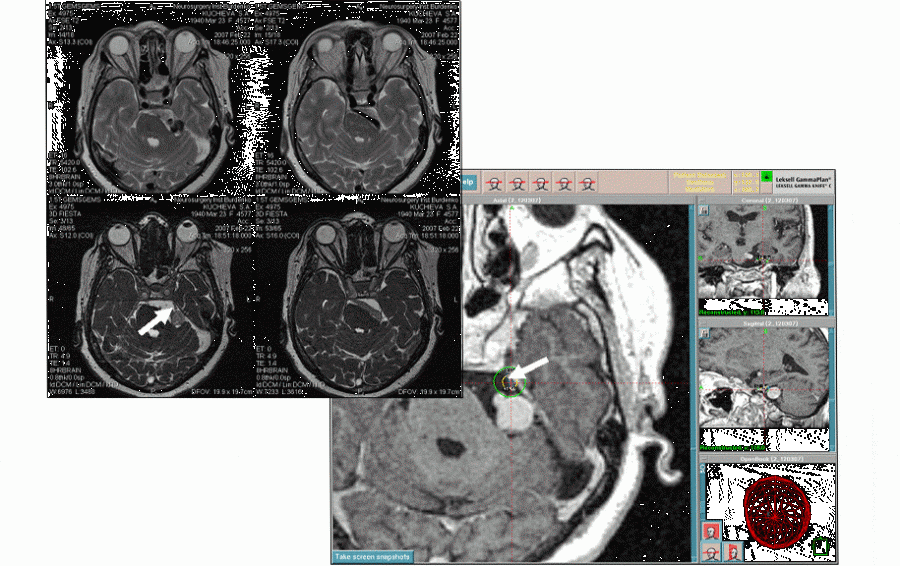

Лечение невралгии тройничного нерва в центре лечения Гамма ножом направлено на облегчение боли и улучшение качества жизни пациента. Существует несколько методов лечения:

3. Хирургическое вмешательство. Если консервативные методы лечения не приносят облегчения, может быть рассмотрено хирургическое вмешательство. Существуют различные хирургические методы, такие как:

- Микроваскулярная декомпрессия: Удаление давления с нерва.

- Радиочастотная абляция: Уничтожение нервных волокон, отвечающих за передачу боли.